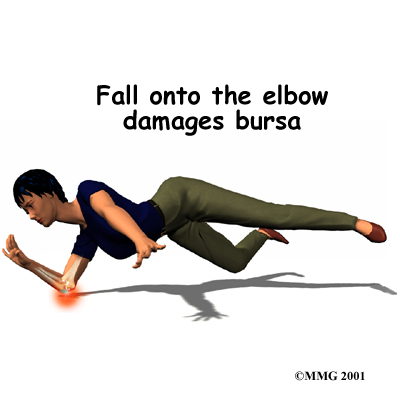

In some cases, a direct blow or a fall onto the elbow can damage the bursa. This usually causes bleeding into the bursa sac, because the blood vessels in the tissues that make up the bursa are damaged and torn. In the skin this would simply form a bruise, but in a bursa blood may actually fill the bursa sac. This causes the bursa to swell up like a rubber balloon filled with water.

In some cases, a direct blow or a fall onto the elbow can damage the bursa. This usually causes bleeding into the bursa sac, because the blood vessels in the tissues that make up the bursa are damaged and torn. In the skin this would simply form a bruise, but in a bursa blood may actually fill the bursa sac. This causes the bursa to swell up like a rubber balloon filled with water.

The blood in the bursa is thought to cause an inflammatory reaction. The walls of the bursa may thicken and remain thickened and tender even after the blood has been absorbed by the body. This thickening and swelling of the bursa is referred to as olecranon bursitis.